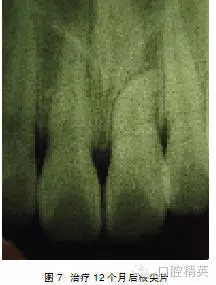

處理:行外科開窗+正畸牽引治療,6個月后破齦萌出,連續(xù)牽引,12個月后到位(圖5~7)。

3.6 支抗和炎癥的有效控制 提供足夠的支抗是牽引埋伏阻生牙入列的保證:可選用較粗的不銹鋼方絲,結(jié)合鏈狀皮圈牽引。粗絲可對抗?fàn)恳Φ姆醋饔昧?,避免造成對鄰牙的傾斜壓入,鏈狀皮圈提供了連續(xù)輕力。如果缺牙較多,覆牙合 較淺、多牙處于剛萌出時期或反牙合,則可采用活動矯治器,在基托上設(shè)計牽引鉤,把牽引的力量轉(zhuǎn)移到腭部和牙槽嵴上。控制炎癥對減少牙齦退縮、邊緣骨喪失也非常重要,矯治過程中,要經(jīng)常檢查埋伏牙的牙周情況,必要時作齦下刮治術(shù)以去除齦下菌斑,防止附著喪失。